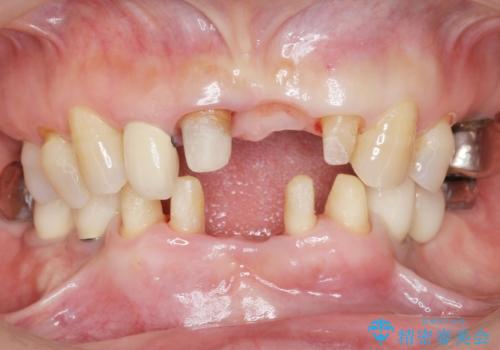

精査したところ、動揺の著しい上下の前歯は重度の歯周病により保存不可能と判断しました。

ブリッジ、インプラント、義歯の選択肢の中で上下前歯ともにブリッジをご希望されました。

抜歯後歯肉の治癒を十分に待ったのち、ブリッジによる補綴治療を行いました。

歯周病が重度であったため抜歯後の歯肉の陥凹が大きく、GBRや歯肉移植による歯周組織の再建をおすすめしましたが、ご希望されませんでした。

上の前歯の再根管治療もおすすめしましたが、必要性を感じないとのことで土台のやりかえだけをご希望されました。